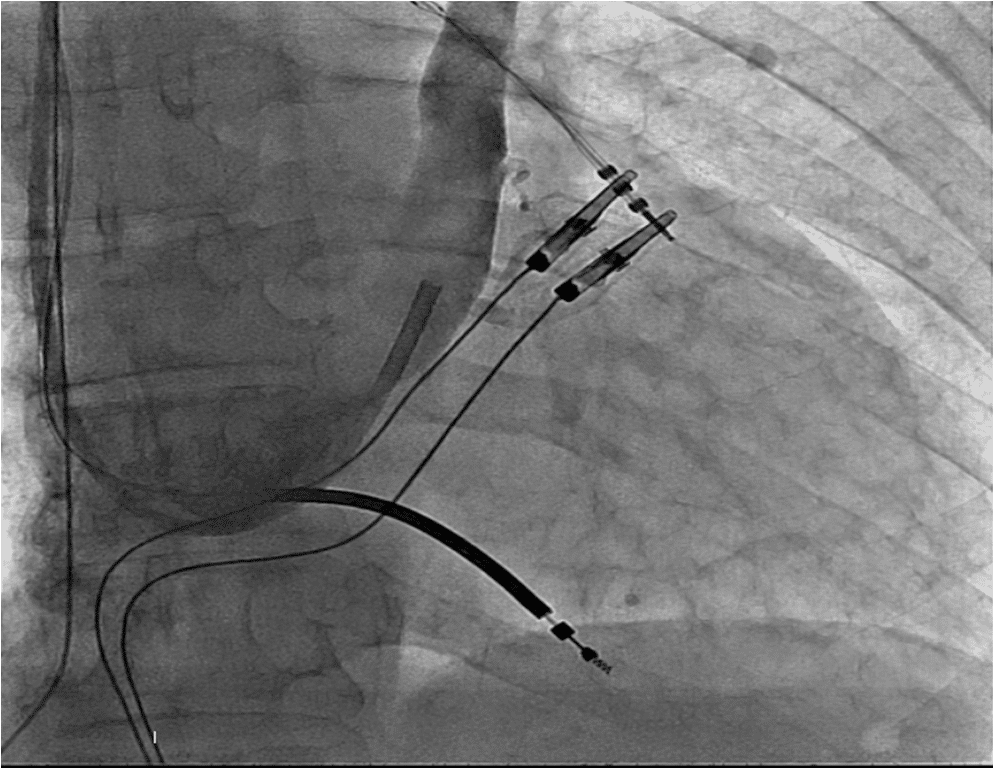

A 75 years old man with an ejection fraction of 35%, QRS duration 155 miliseconds and LBBB morphology on surface electrocardiogram was shedduled for CRT-D device implantation. Venography was performed as a part of our routine practice in order to explore the patency of the subclavian vein. After being sure about the patency of the vein, a pocket was created in the left pectoral region. The vein was canulated but the attempt to advance the guidewire has aborted. The tip of the guidewire fastened on a steep angle through the course of the vein. The venography was looked on again. Presence of a regressed innominate vein in a tapered aspect was noticed as well as a downward flow on the left side of the view . The patient had a PLVCS. Venography using the right antecubital vein showed the presence of a patent right SVC. A new pocket was created on the right pectoral region. Atrial, right ventricular and left ventricular leads were implanted using the right axillary vein puncture (Figure 1, 2). The procedure was quite straightforward and carried out succesfully (Figure 3).